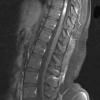

MYELIN (IMMUNE-MEDIATED)

NMO (Neuromyelitis Optica)

NMO Spectrum Disorder (8)